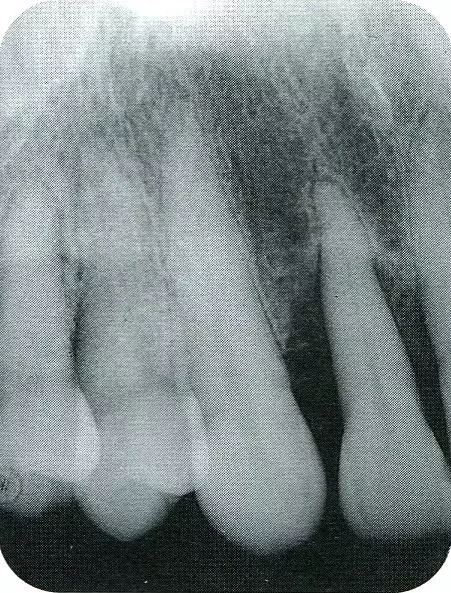

案例3   針對3壁性垂直性骨缺損使用非吸收性膜進(jìn)行再生治療,再翻瓣時進(jìn)行骨形態(tài)修整的病例。

▲圖7-1  左下6近中可觀察到3壁性垂直性骨缺損。此病例考慮到齦瓣供血關(guān)系,在前磨牙部位進(jìn)行了減張切開,沒有進(jìn)行縱切開。并利用刮治器、牙周外科用車針進(jìn)行了徹底的骨缺損部位搔刮。